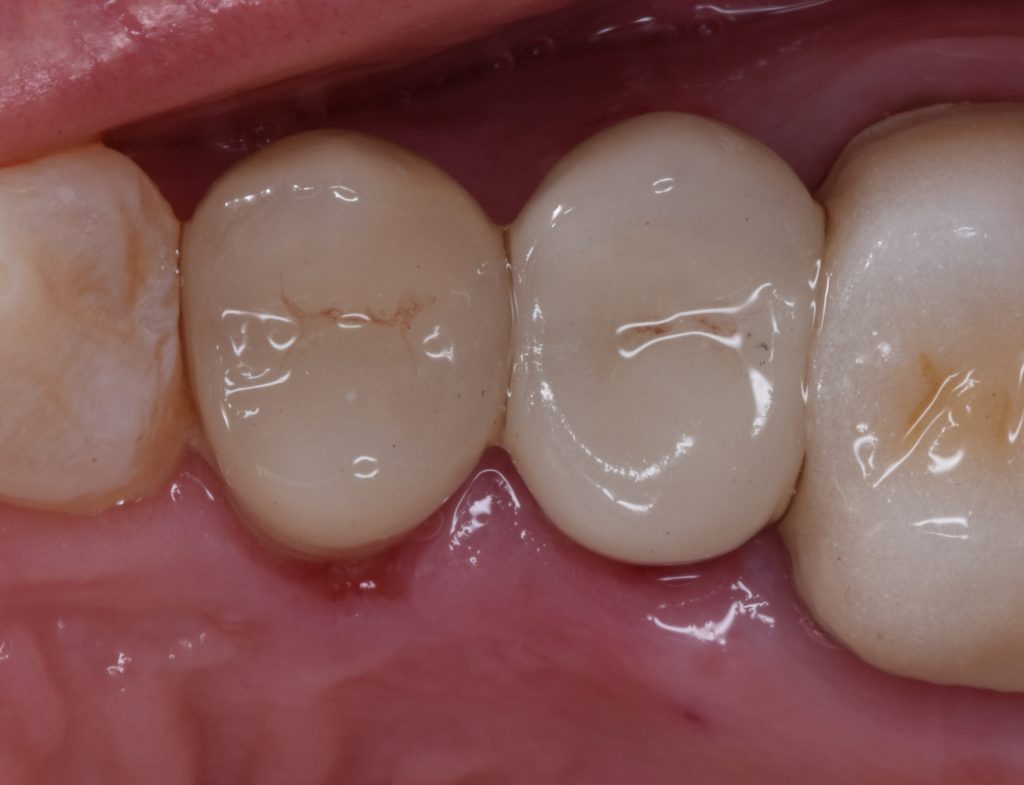

I decided to go for indirect lithium disilicate restorations

And final design to receive to monolithic lithium disilicate restorations

Cementation by heated composite

Shofu beautifill LS